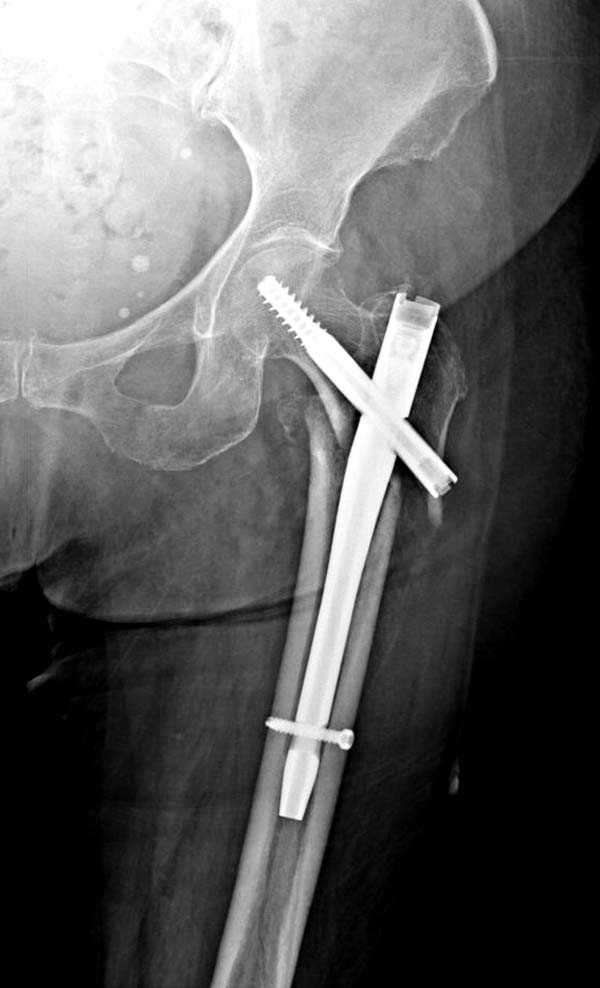

Для лечения переломов проксимального бедра существует различные конструкции, включая цефаломедуллярные. Среди них из-за простоты и удобной конструкции распространенным является Gamma.

Имплант засчет верхней блокировки создает эффект угловой стабильности и применяется не только при скоростных травмах у молодых, а также для лечения переломов пожилого возраста.

Здесь представлен случай, где в послеоперационном периоде обнаружена техническая ошибка, Gamma 3 установлен с нарушением методики. Больная в 91 лет, прооперирована через день после поступления и выписана через 48 часов.

При первом послеоперационном поликлиническом осмотре больная предъявила жалобы на боли в бедре. В серийных снимках обнаружен продольный перелом верхнего отдела бедра.

Считаем, что техническая ошибка произошла во время установки гвоздя, когда рассверливанию канала не уделили должного внимания. Канал остался узковат, и гвоздь был забит с силой. Полная нагрузка конечности приостановлена на две недели, и боли в конечности изчезли. Больная начала нагрузку и перелом срастается.-- Djoldas Kuldjanov, M.D.Associate ProfessorDepartment of Orthopedic SurgerySt. Louis University

I have a different interpretation of this case. I suspect you did not tighten the set screw all the way in order to allow sliding of the lag screw and fracture fragment compression, as you would for a standard intertrochanteric hip fracture. This is a reverse obliquity fracture, so the result is migration of the proximal segment. I doubt reaming the canal would have prevented this. Had the set screw been fully tightened, there would be no postoperative fragment motion.

I looked at the films again and saw that you are referring to the nondisplaced shaft fracture, not the proximal fragment position. Sorry.

Мне тоже представляется, что это не единственная проблема. Продольные трещины заживают легко и быстро. Интересно, почему увеличился варус и

появилась медиализация дистального отломка.

Мне думается, что варусное положение проксимального отломка на последующих снимках не более чем проекционный феномен. Раскол же диафиза вдоль, наверняка, связан с чрезмерно насильственным введением штифта. Вообще, при реверсивных, да и обычных вертельных переломах, многие давно отказались от короткой Гаммы в пользу long-версии. Но в любом случае надо быть на 100 уверенным в подготовке канала.